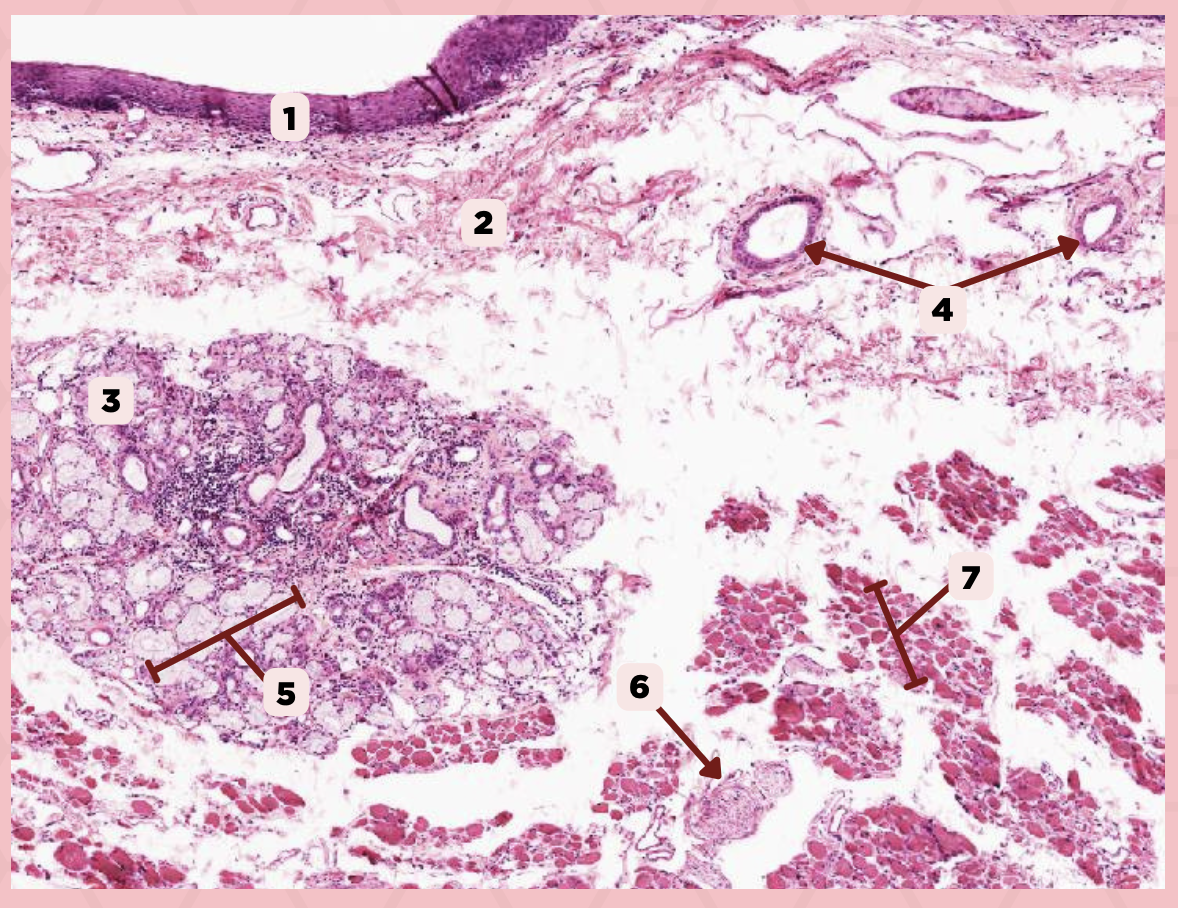

Cheek

Identify the specimen.

Mucosa

Identify the structure labeled as 1.

Lamina Propria

Identify the structure labeled as 2.

MALT

Identify the structure labeled as 3.

Blood Vessels

Identify the structure labeled as 4.

Buccal Glands

Identify the structure labeled as 5.

Nerve

Identify the structure labeled as 6.

Muscle Fascicles

Identify the structure labeled as 7.